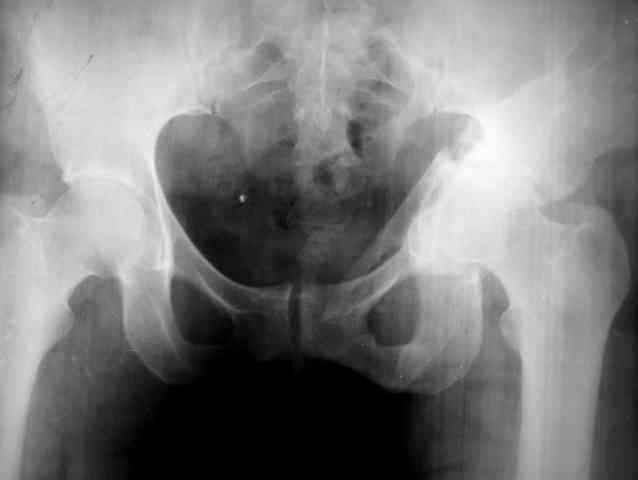

Ув.коллеги,нужен совет по представленному случаю. Пациентка, 50лет. В 2003 году в результате дтп получила перелом вертлужной впадины. 1.5 месяца находилась на скелетном вытяжении, в дальнейшем до 10 месяцев после травмы ходила без опоры на конечность. Вернулась к труду, но в 2006 году перешла на инвалидность и была поставлена в областную очередь эндопротезирования. В данный момент уже находится в отделении, но, судя по рентгенограммам и данным КТ, сращения на уровне перелома не произошло. Что предпочесть? 1.Остеосинтез с костной пластикой и последующим эндопротезированием. 2."Октопус". 3.Кольцо Мюллера. Заранее благодарен за ответы и ценные замечания.

Окончательное решение примете в ходе операции эндопротезирования . Наилучшее и вероятное решение - эндопротезирование бесцементной чашей хорошего размера с костной пластикой по типу "замельчения" дна вертлужной впадины, и с выведением центра вращения на естественное место (то есть кнаружи).

Возможный вариант - антипротрузионное кольцо (Октопус или Бурш-Шнайдер или....) и костная пластика дна впадины, но это если таз здесь нестабилен клинически,. тогда само кольцо будет фиксатором для остеосинтеза, а трансплантаты - материалом для последнего. Моделирующее кольцо Мюллера - нет, просто остеосинтез - нет. Бедренный компонент - без особенностей.